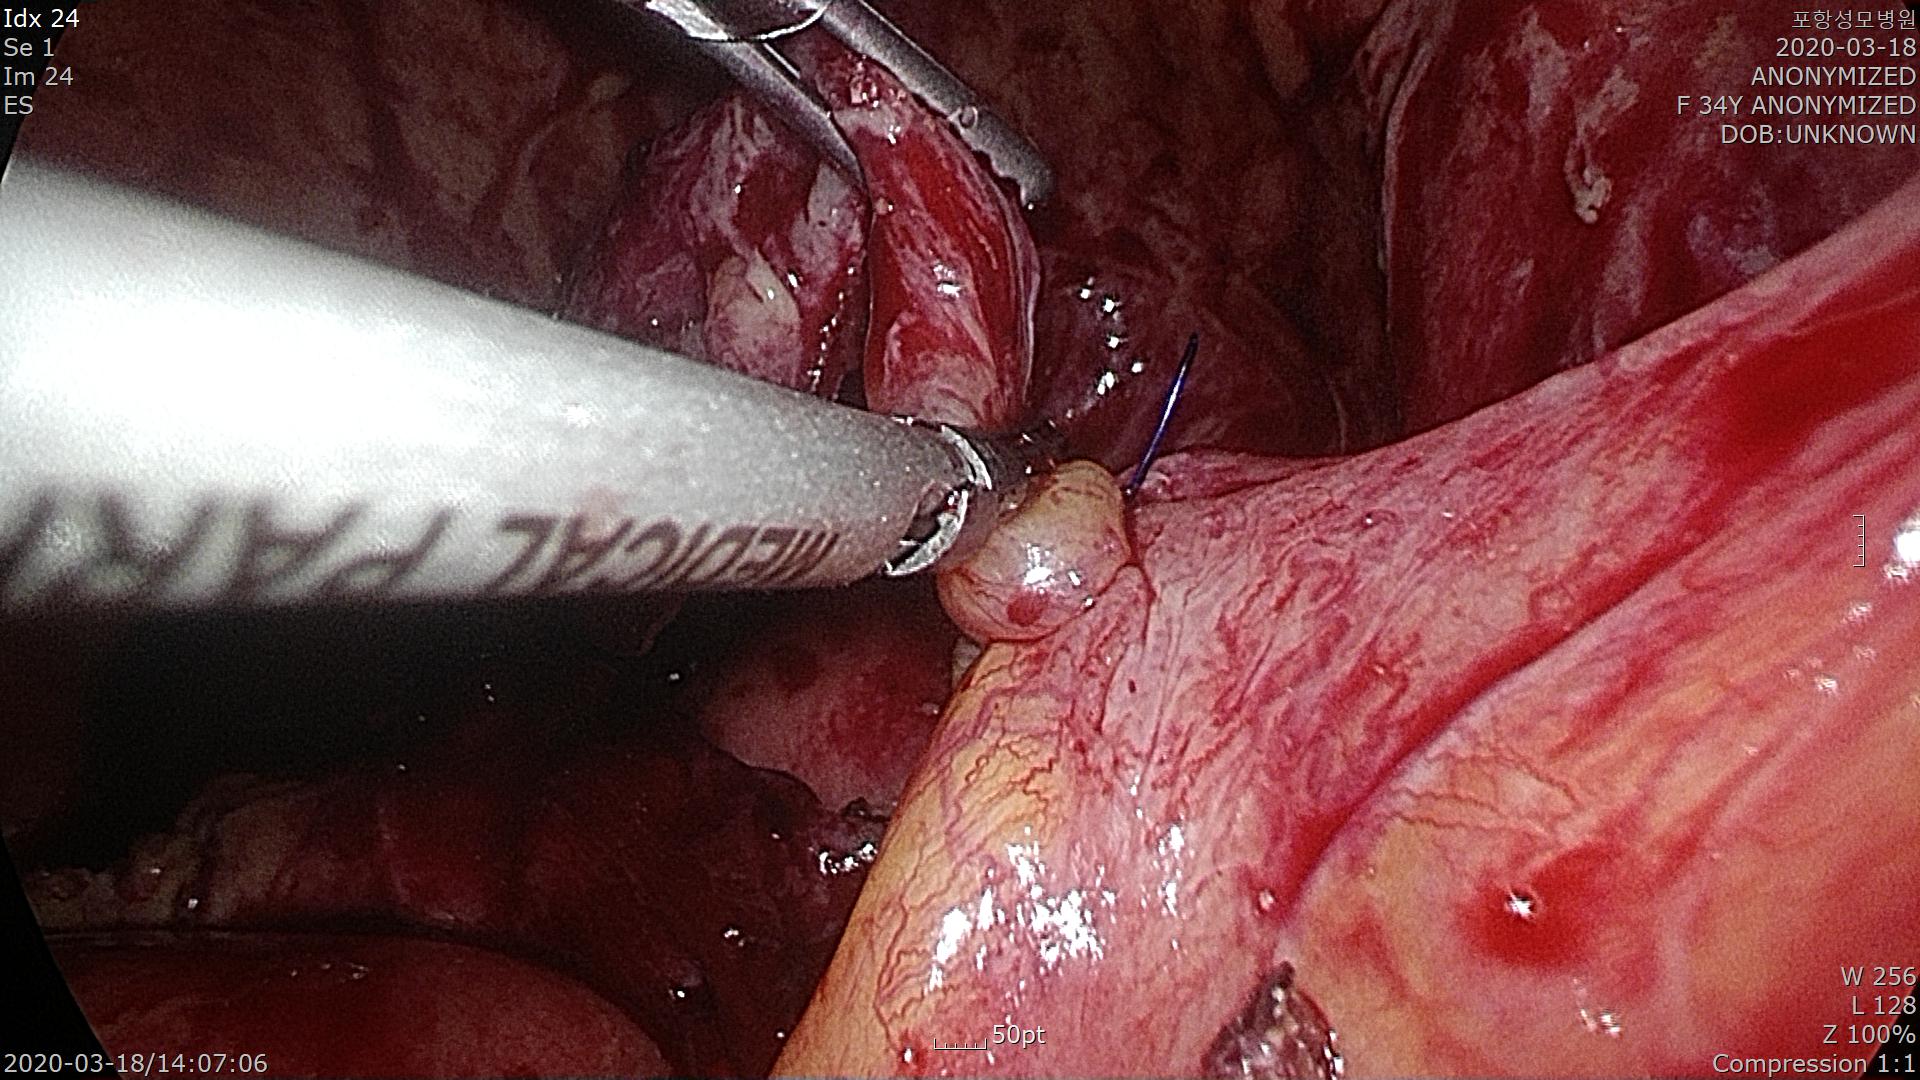

충수돌기가 완전히 노출된 모습입니다.

충수돌기의 대장 연결부위를 Endo-loop(충수돌기 기저부를 결찰하는 제품명)를 이용하여 결찰합니다.

결찰된 충수돌기 원위부를 절제해 냅니다.